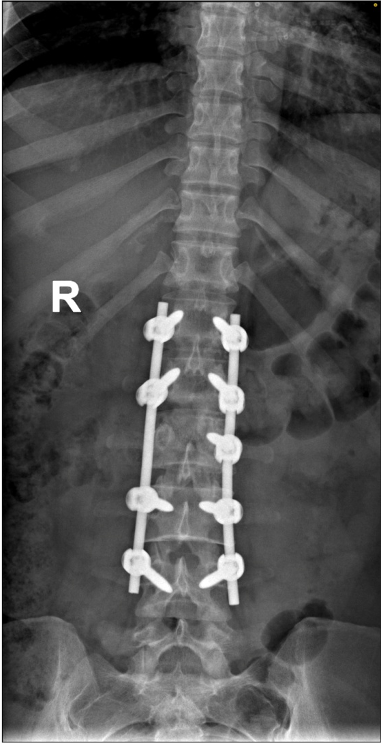

2. Surgical Intervention:

– Drainage: Abscesses may need to be drained surgically.

– Debridement: Removal of infected tissue and bone.

– Spinal Stabilization: In cases of spinal instability, surgical stabilization may be required.